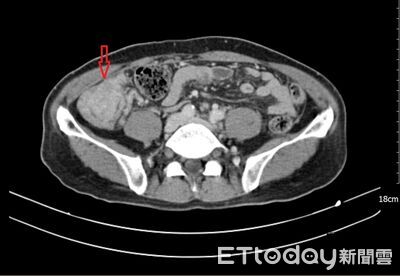

66歲陳先生半年前陸續出現全身倦怠、食慾不振、腹脹與腹瀉等情形,短短2個月暴瘦6公斤,就醫診斷出「多發性結腸癌」,且腫瘤已擴散至腹腔。義大癌治療醫院評估後,先安排陳先生接受化療,後續再接受高壓氣霧化療、腫瘤減積手術清除病灶,陳先生術後恢復順利,目前體力、活動能力逐步改善,這份研究成果登上國際期刊,再次顯示台灣醫療領域的臨床經驗與學術能量。 《詳全文...》